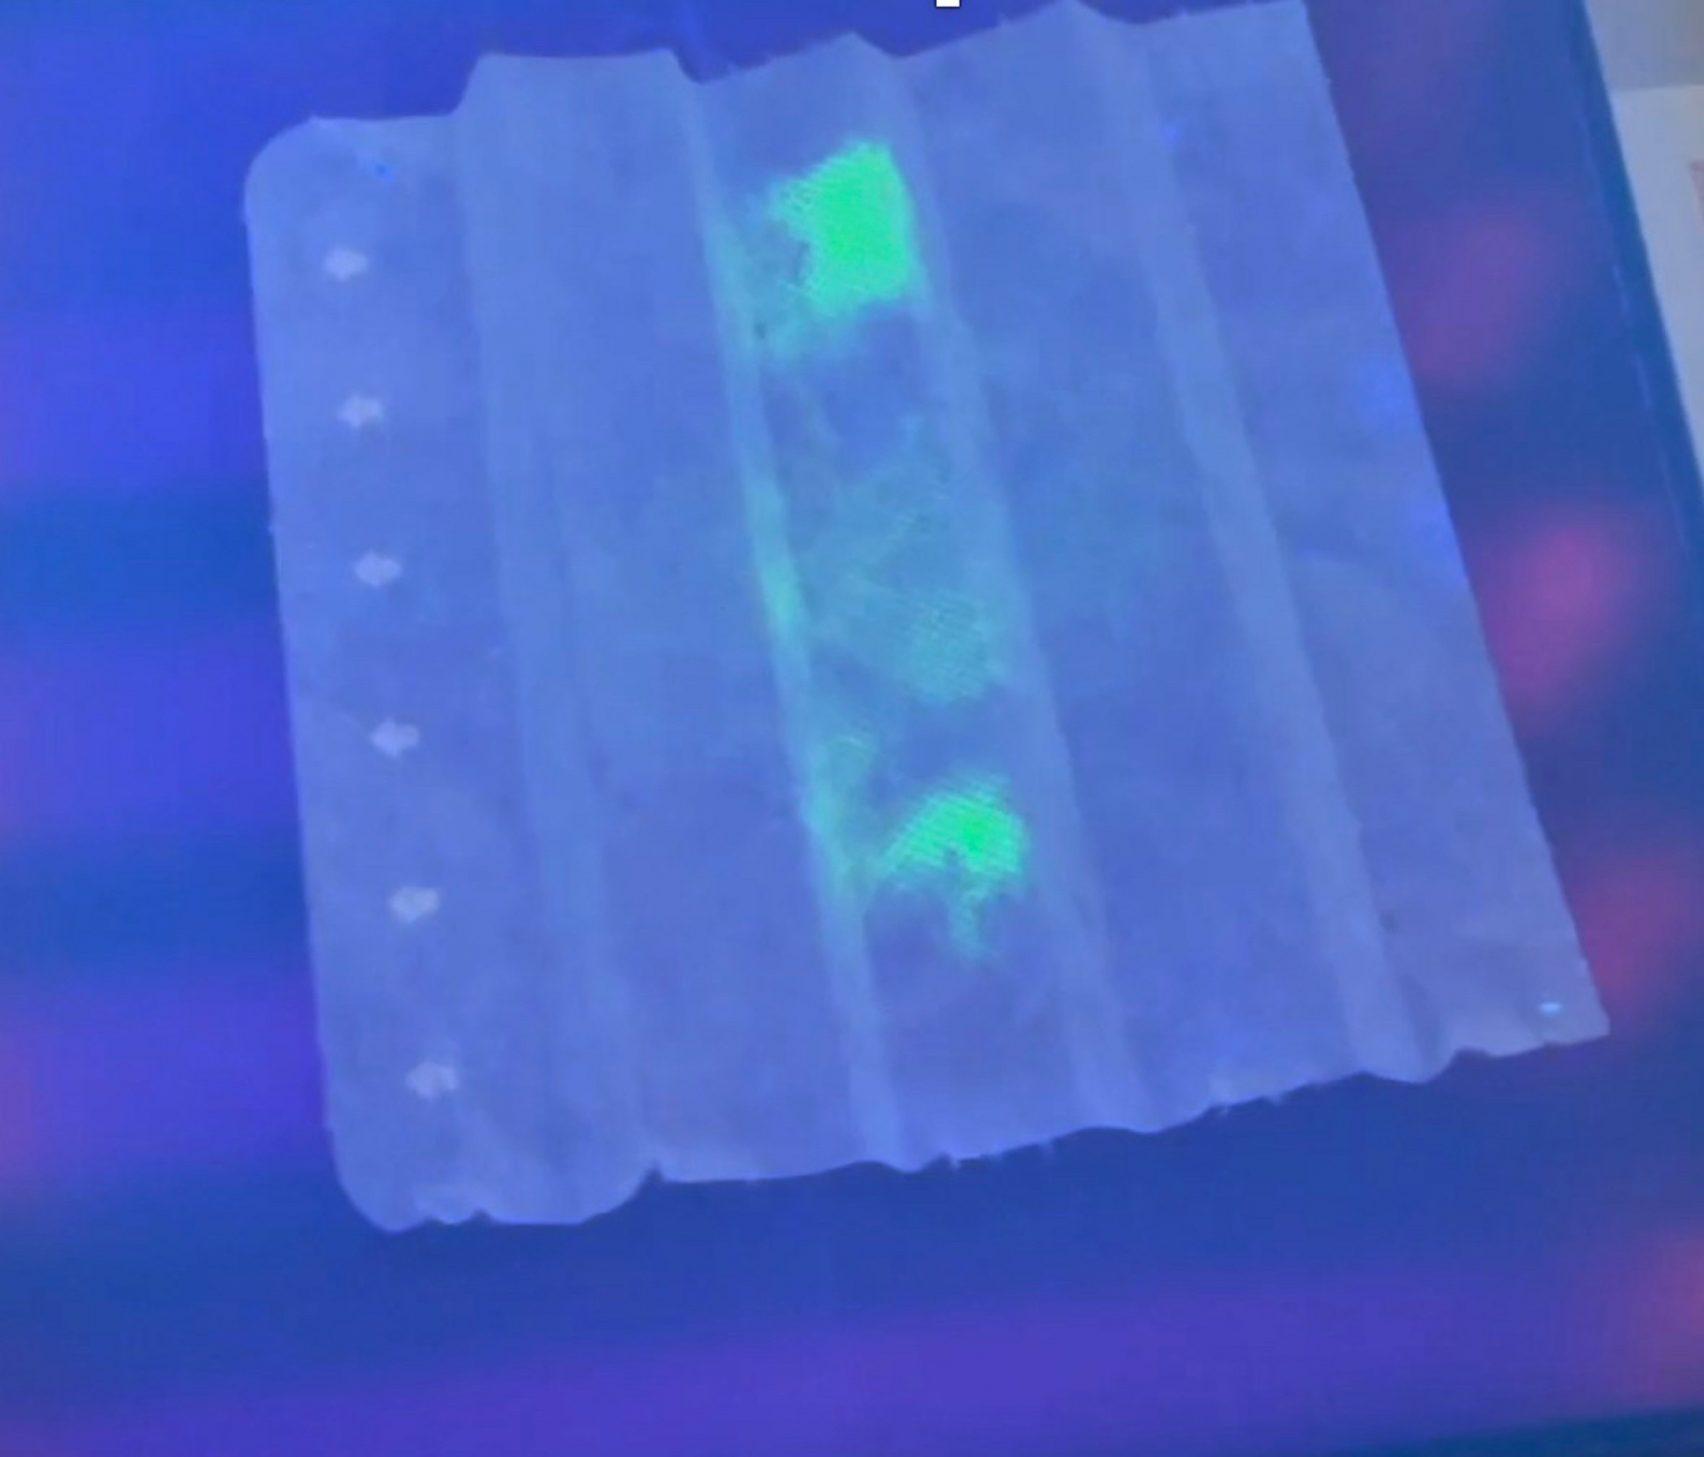

პირბადეში მოთავსებულია სპეციალური ფილტრი, რომელიც კორონავირუსის დაფიქსირების შემთხვევაში ანათებს. უკვე ჩატარდა შესაბამისი კვლევები და ახალი გამოგონების ეფექტიანობა მათ შედეგად უკვე დადასტურებულია.

მკვლევარს იმედი აქვს, რომ მსგავსი ტექნიკის საშუალებით, სხვა ვირუსებისგანაც მოვახერხებთ თავის დაცვას. ჯერჯერობით, სირაქლემას ანტისხეულებიანი ფილტრები მხოლოდ ულტრაიისფერი გამოსხივების ფონზე ანათებენ.